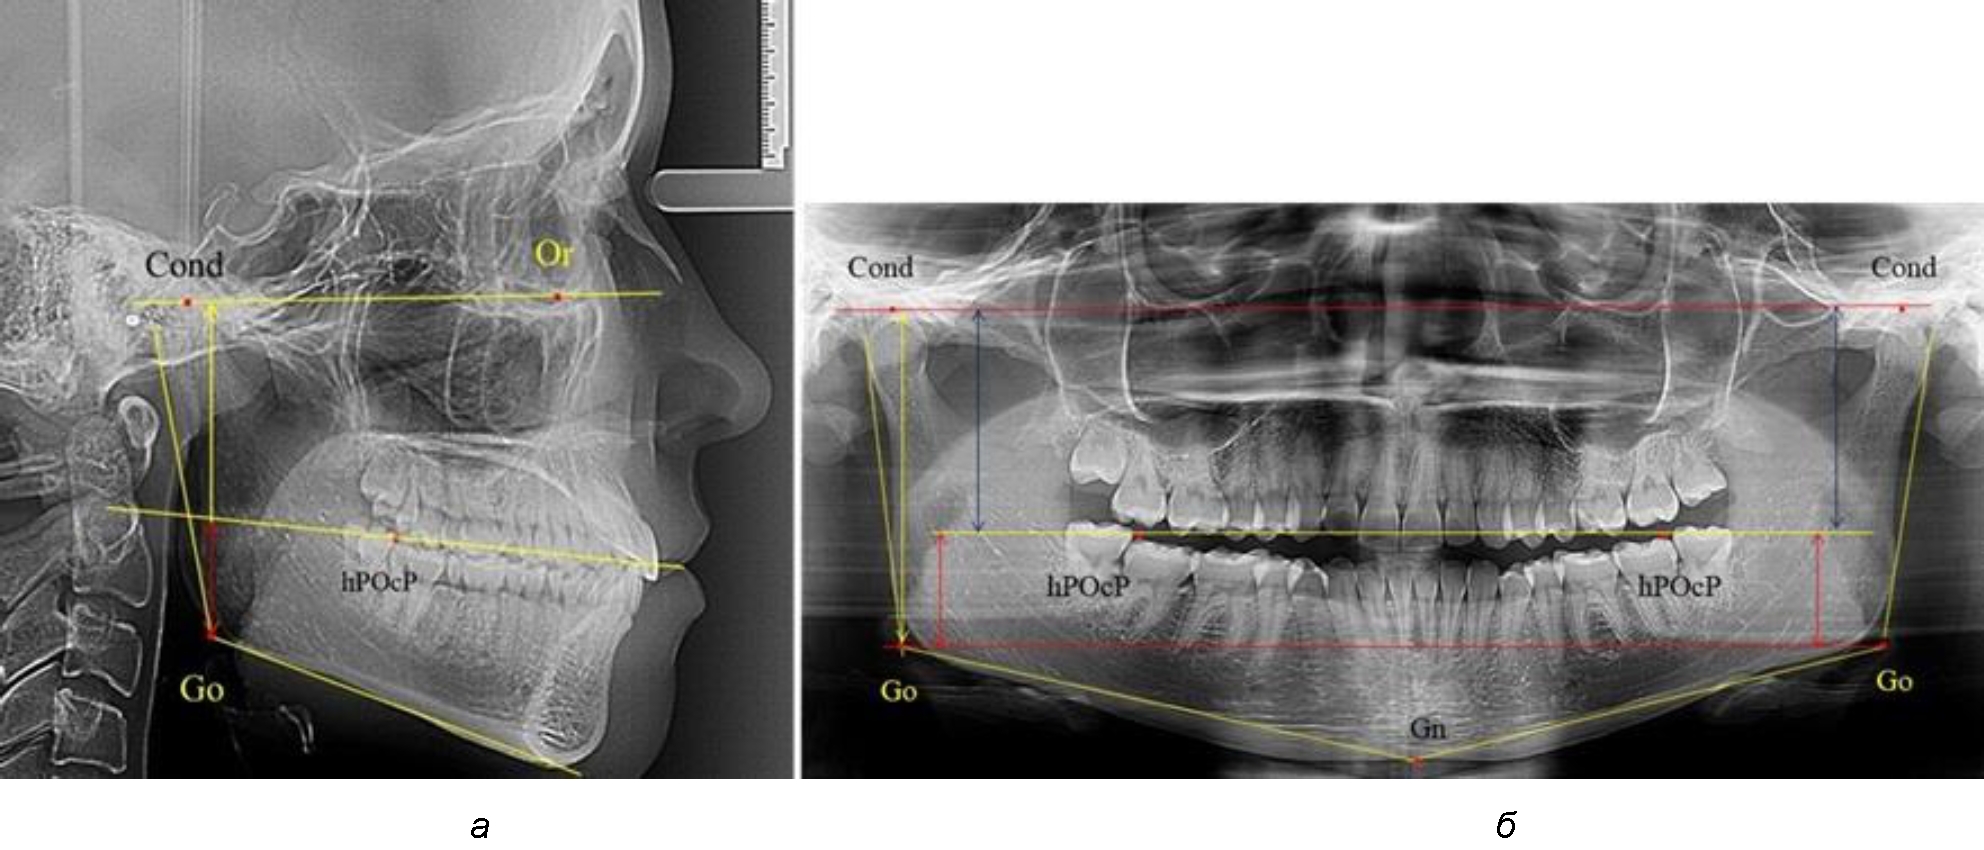

Рис. 1. Метод измерения высоты ветви нижней челюсти на телерентгенограмме (а) и ортопантомограмме (б)